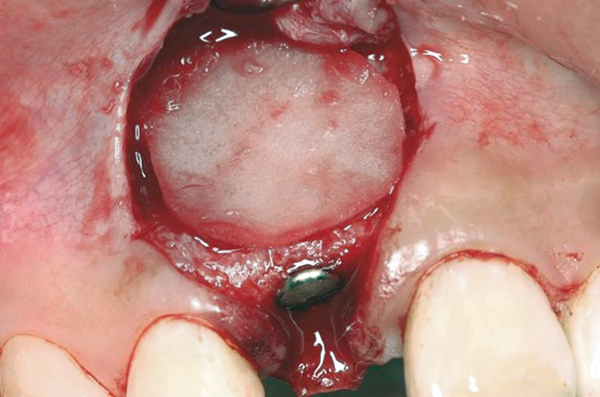

Fig 6. Collagen barrier positioned over bone graft.

Figure 6